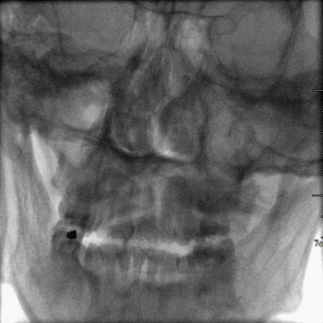

头颈CTA :左侧颈内动脉末端及基底动脉重度狭窄或闭塞。

术前CTA检查。

诊断:急性脑梗死(椎-基底动脉系统)、基底动脉闭塞、左侧颈内动脉末端次全闭塞。